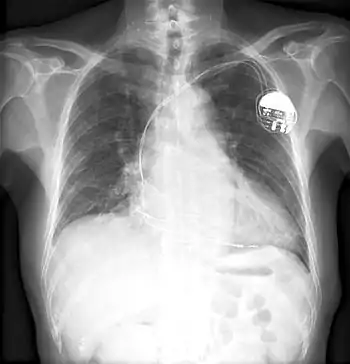

A chest x-ray of a pacemaker

Other notable inventions include a variable resistor used in guided missiles.[15] His most famous invention was likely a control unit for the artificial cardiac pacemaker.[4] The device essentially uses electrical impulses to maintain a regular heartbeat. Among his other inventions is a burglar-proof cash register.[16]